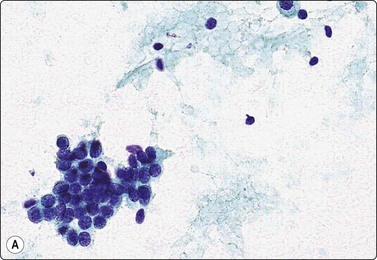

Fig. 7.1 Radiation-induced atypia

(A) The epithelial cells in this irregular cluster show considerable nuclear enlargement, pleomorphism and hyperchromasia, but also some degenerative changes such as loss of nuclear structure (MGG, HP); (B) Corresponding tissue section (H&E, IP).